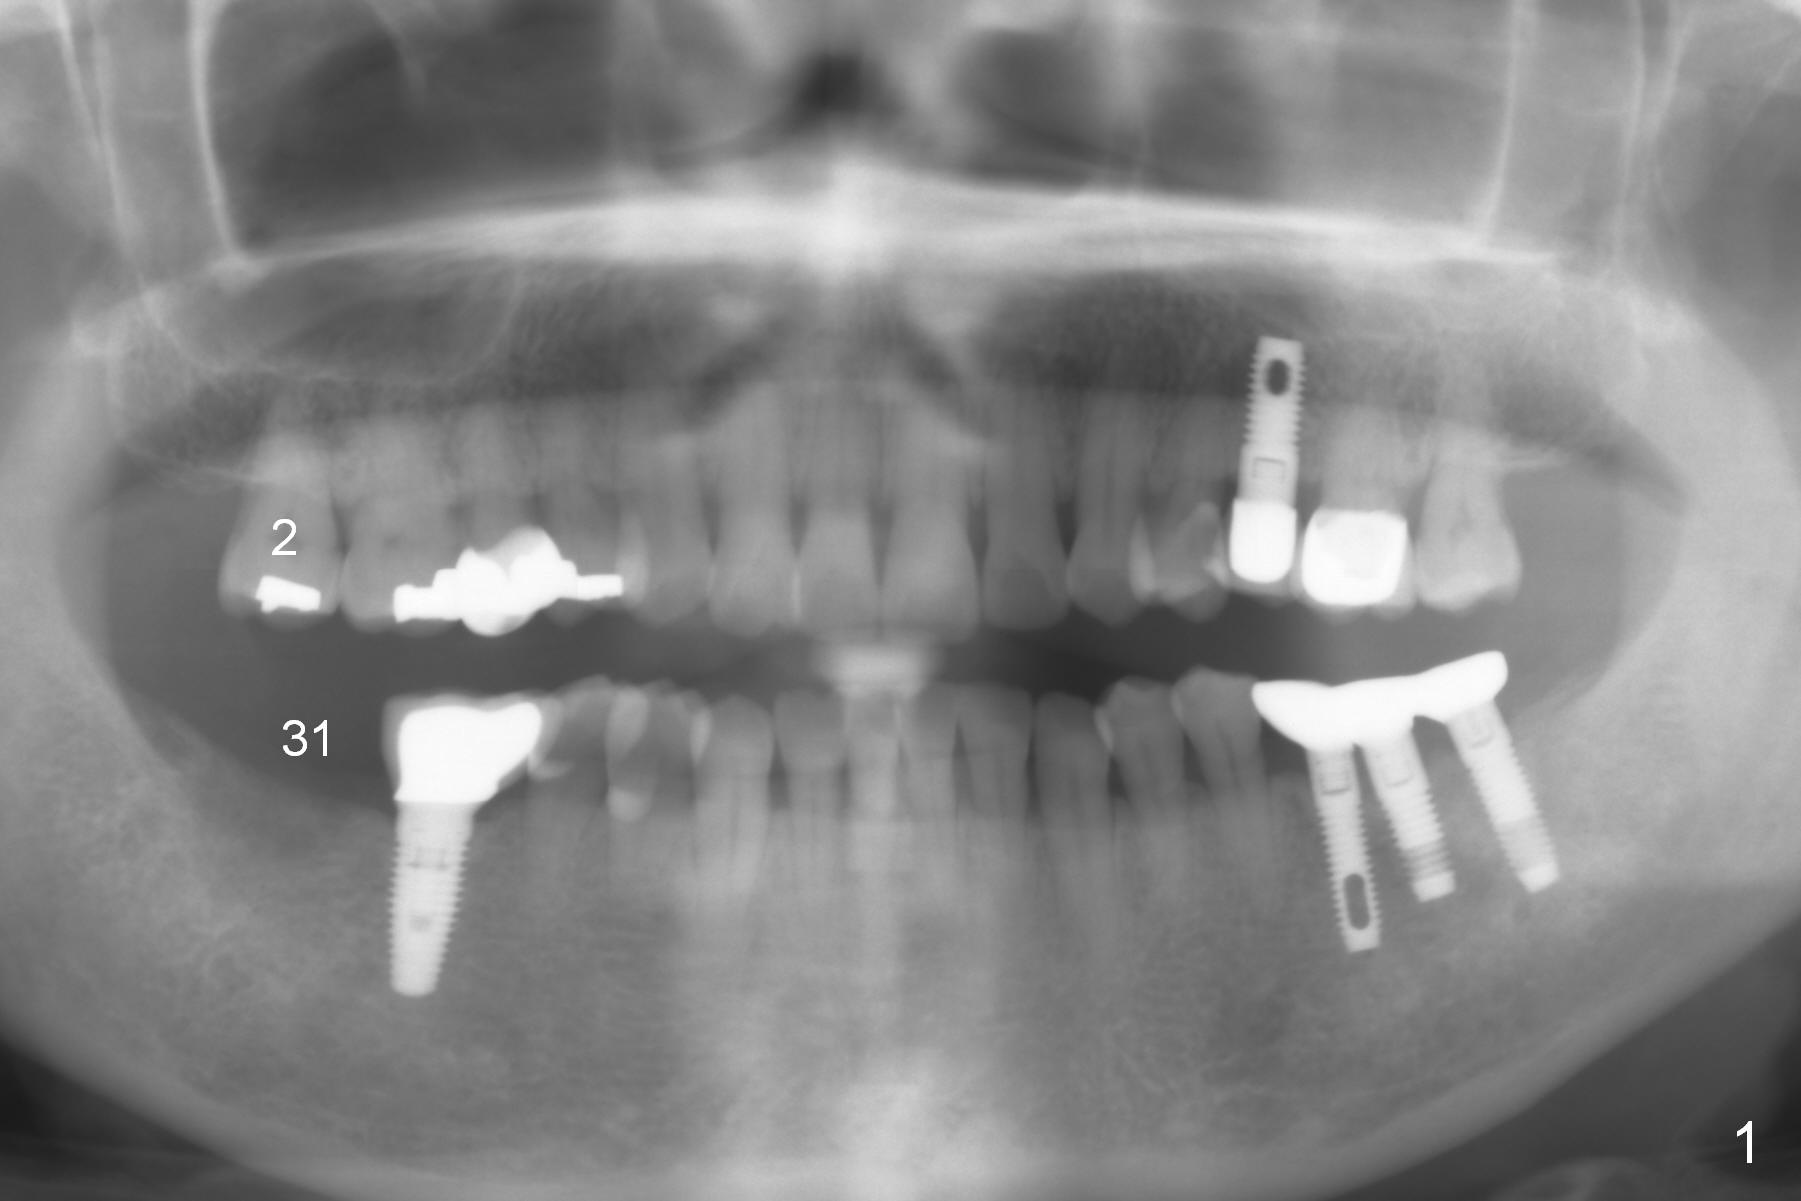

A 62-year-old woman requests #31 implant placement ~ 1 year post extraction (Fig.1). The opposing tooth (#2) appears to have not supraerupted. The socket outline at #31 is visible (Fig.2,3 red dashed line). The initial osteotomy (green) should bisect the socket and be perpendicular to the posterior mandibular slope (pink). The stopper is set at 10 mm with sufficient clearance from the superior border of the Inferior Alveolar Canal (yellow dashed line). Take PA for confirmation and make necessary adjustment. The implant is either 5x17 mm (tissue-level) or 5x13 or 14 mm (bone-level).